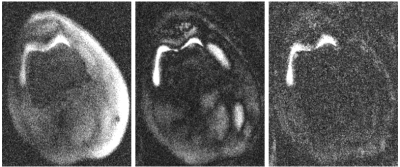

Fig. 2 Animation showing sampling from the learned prior. The score model is run independently with random initializations. This shows the score model's ability to generate images from the learned distribution. The model starts with gaussian noise and uses Annealed Langevin Dynamics to sample from the prior distribution.

Fig. 3 Animation of the posterior sampling reconstruction process. Images are shown at each iteration for the three basis coefficient images.